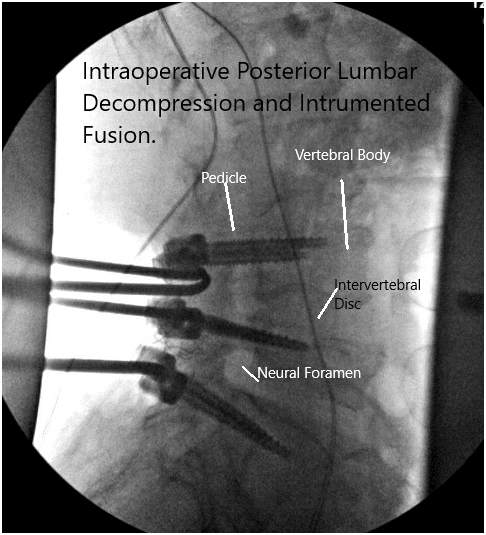

Intraoperative fluoroscopy images.

Transpedicular histopathology was sent from the left L5 body, transpedicular. The patient was taken to the operating room where generaI anesthesia was induced. A Foley catheter was passed. Needles for neurophysiological monitoring in the form of EMG, somatosensory monitoring as well as pedicle screw stimulation was done.

The lamina of L5 was marked and a Woodson was passed into the lamina of L4 and a C-arm picture was taken to confirm our levels. After confirmation of levels. further dissection was carried out to the facet joints of L3-L4 from L4-L5 and L5-S1.

Now the pedicle screws for the S1 were planned and the pedicle of S1 was probed from either side and checked under C-arm. After finding an acceptable position. The pedicle screw of 6 mm x 45 mm cortical fix screw was put on both pedicles of S1.

The pedicles of L5 were cannulated now and the position of the probe was checked under the C-arm and found to be acceptable and biopsy material was sucked out using a Jamshidi needle from the right pedicle of LS. Some tissue and bone marrow aspirate was sent for biopsy. A 6 mm x 40 mm cortical fix screw was inserted on both pedicles of L5.

The pedicles of L4 were cannulated similarly and checked under C-arm and found to be acceptable. A 6 mm x 45 mm cortical fix screw was inserted on both pedicles of L4. The screw heads were lined well on both sides. The wound was washed copiously with normal saline mixed with Bacitracin and gentamicin.

The screws were lined and rods were placed on both sides and tightened to the screw heads. The final pictures of the screw were taken with C-arm and saved. Hemostasis was achieved. Vancomycin antibiotic was sprinkled into the wound. Considering the durotomy a deep suction drain was not put. The closure was done in layers. Two suprafascial drains were put. The counts were completed, checked, and correct at the end of the procedure. The patient was transferred into a supine position on the bed, extubated, and moved to the postoperative care unit in a stable condition.